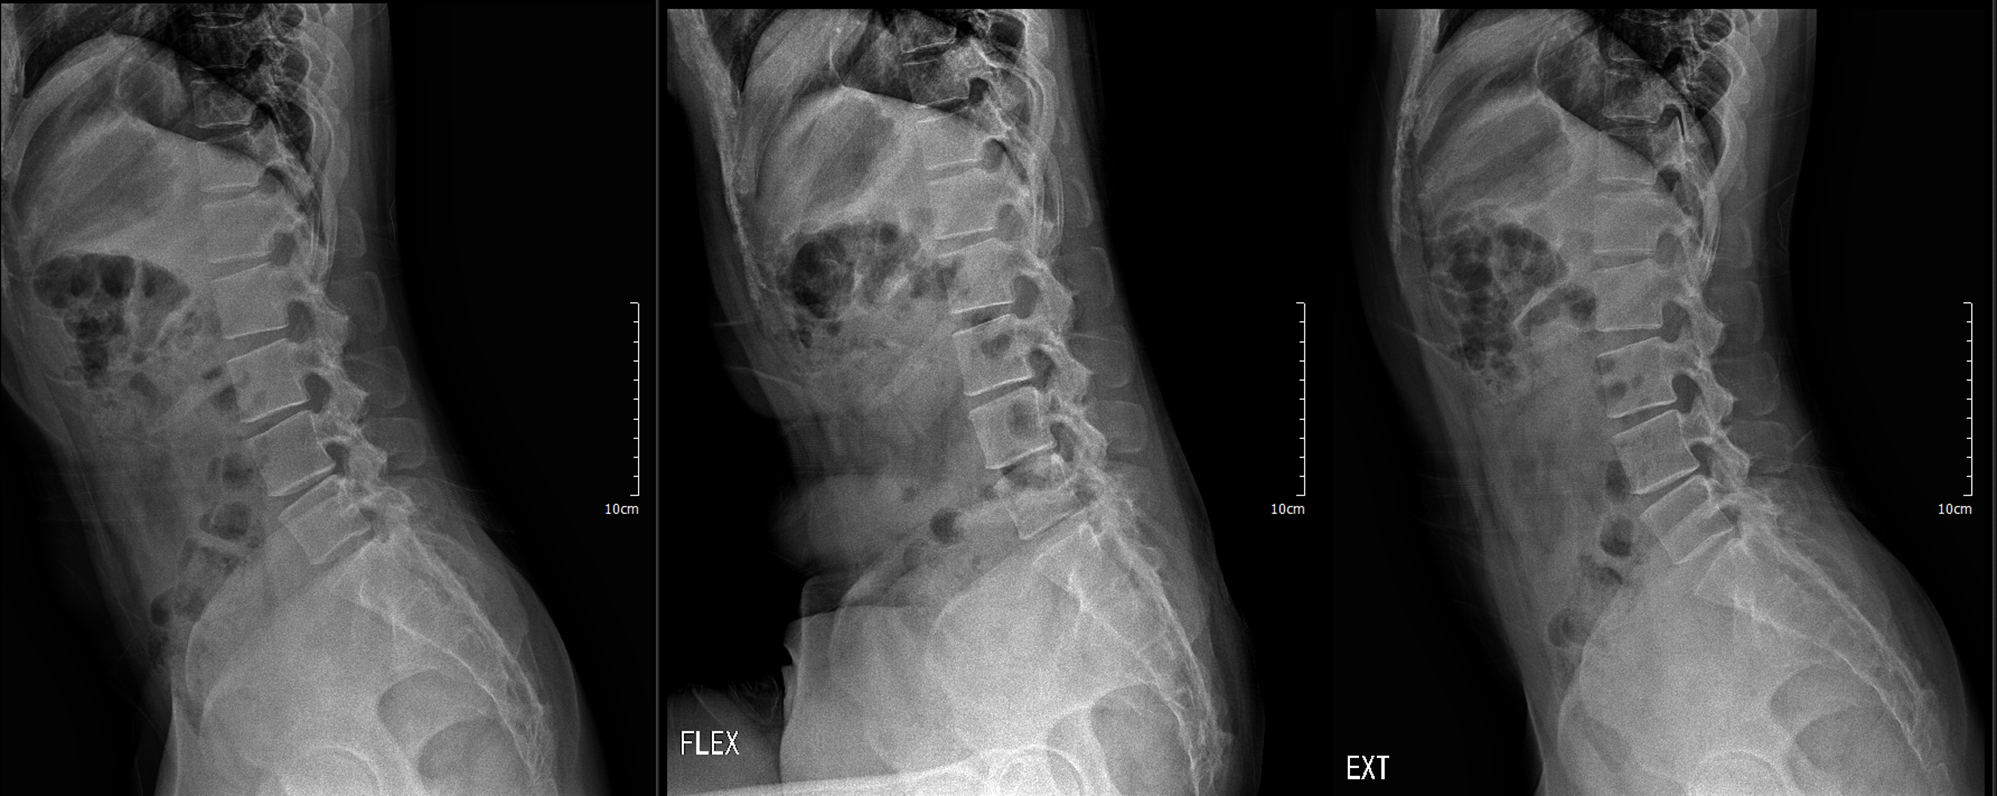

이번에 촬영한 x ray

디스크 간격이 좁은 곳 확인

L3/4 4/5